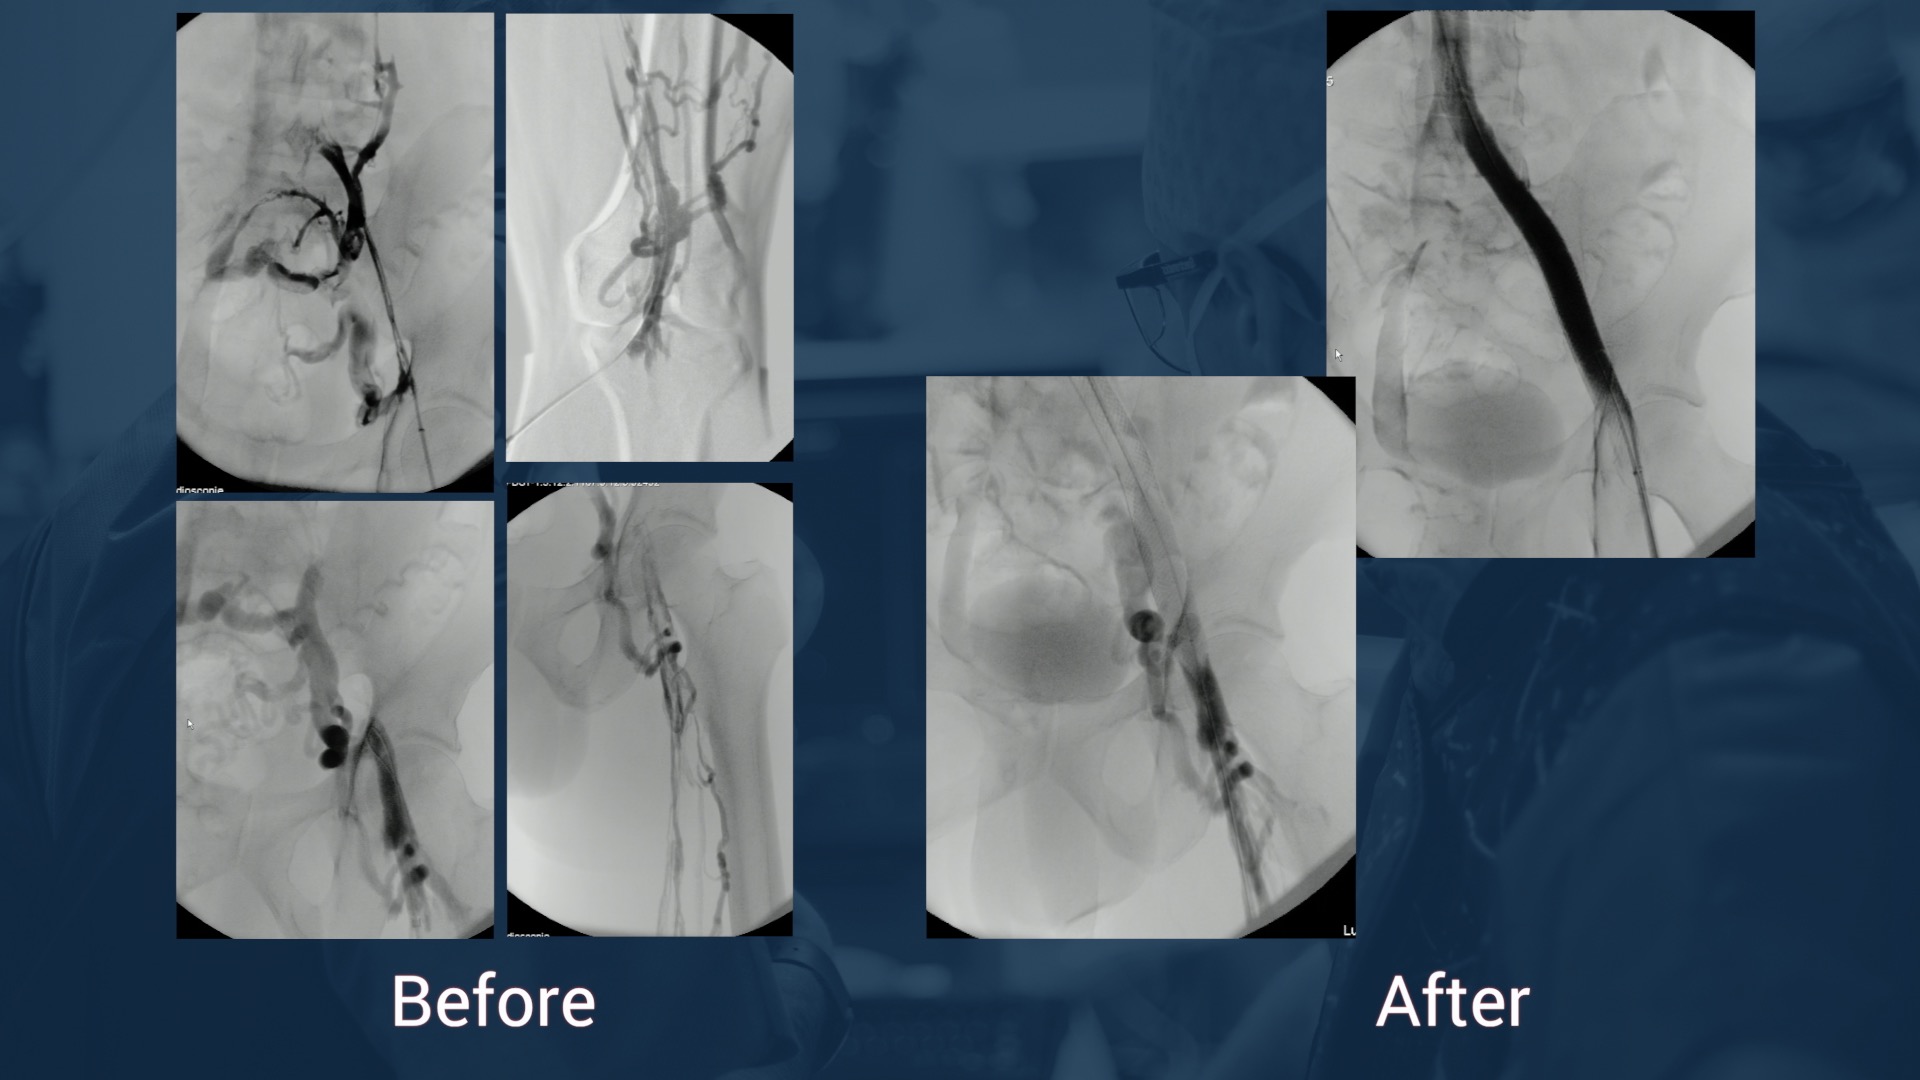

Clinical Data

• Female, 80 years old

• LFI DVT March 2016

• C3s (tight diameter +4cm) + venous claudication

• Duplex scan :

• LFIV obstructive lesions with LCIV occlusion

Attempt of recanalization with previous surgical thrombectomy

Dr Hartung & Dr Neglen - Decision of non-intervention after diagnostic